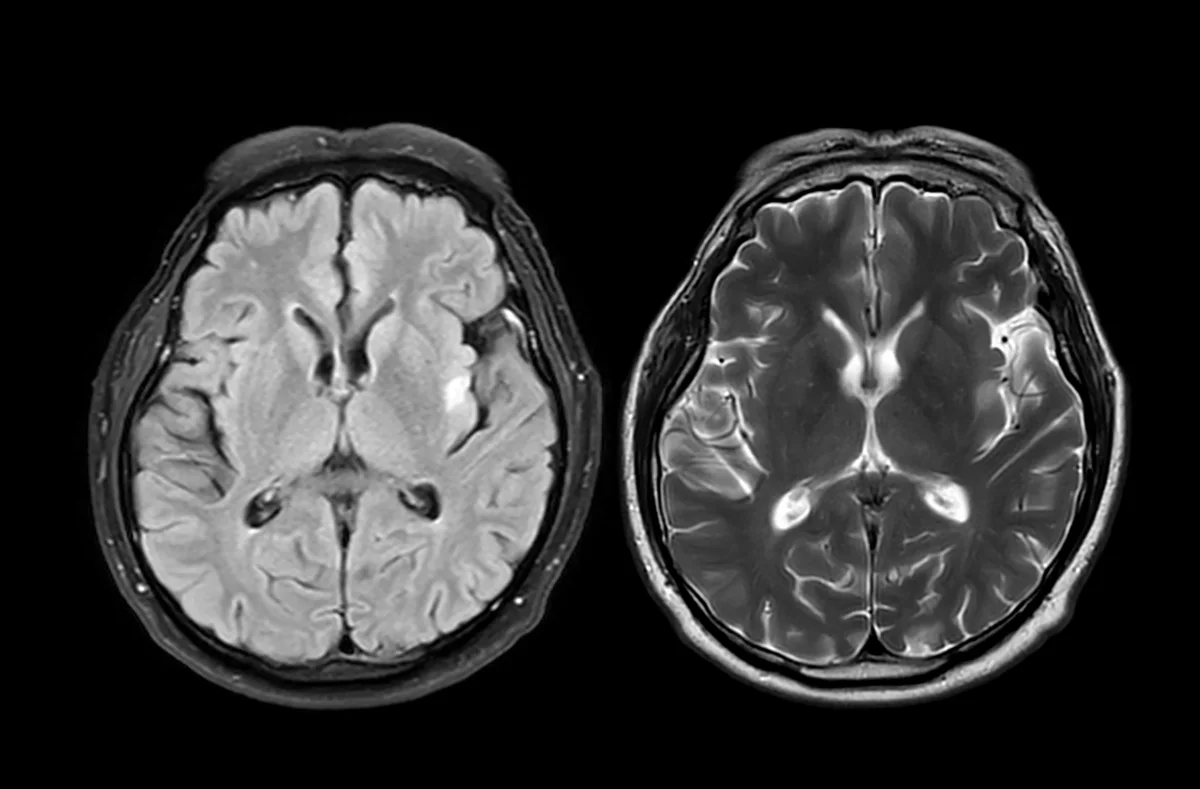

This video is part of “Innovations In: RSV," an editorially independent special report that was produced with financial support from MSD, Sanofi and AstraZeneca. Zachary Rubin: Has the pandemic aged your brain? A new study suggests the answer might be yes, even if you never got sick with COVID-19. On supporting science journalism If you're enjoying this article, consider supporting our award-winning journalism by subscribing. By purchasing a subscription you are helping to ensure the future of impactful stories about the discoveries and ideas shaping our world today. Researchers in the U.K. analyzed brain scans from nearly 1,000 healthy adults before and during the COVID-19 pandemic. What they found was surprising: people living through the pandemic showed signs of accelerated brain aging. Their brains appeared about five and a half months older than expected when compared to prepandemic trends. That’s right, just living through the stress and disruption of the pandemic may have left a subtle, measurable imprint on your brain. So how did they figure this out? The scientists used data from the U.K. Biobank, a massive health database that includes brain imaging from tens of thousands of participants. They trained a machine-learning model to estimate “brain age” based on hundreds of structural features seen in MRI scans. Then they compared two groups: people who had both scans before the pandemic and those who had one scan before and one during the pandemic. The result? Brain aging accelerated in the pandemic group, even among people who didn’t get COVID-19. Now here’s a twist: while the structure of the brain appeared older, cognitive function—things like processing speed and problem-solving—didn’t necessarily decline in people who avoided infection. The structural changes didn’t always mean someone felt or performed worse, at least not right away. So what’s causing this? The researchers propose two possibilities. First, actual infection with COVID-19 can cause lasting effects on the brain. That’s already been shown in previous studies. But the second possibility is broader and maybe more troubling: the pandemic environment itself may have triggered the change. Think about it: social isolation, chronic stress, loss of loved ones—all of that may contribute to brain changes over time. The good news? You can take steps to support your brain health today. Stay physically active. Keep your brain stimulated. Prioritize sleep, good nutrition and social connection. And yes, get vaccinated and stay protected. COVID-19 infections, especially repeat ones, are still associated with long-term cognitive effects. Your brain has been through a lot, so treat it kindly.